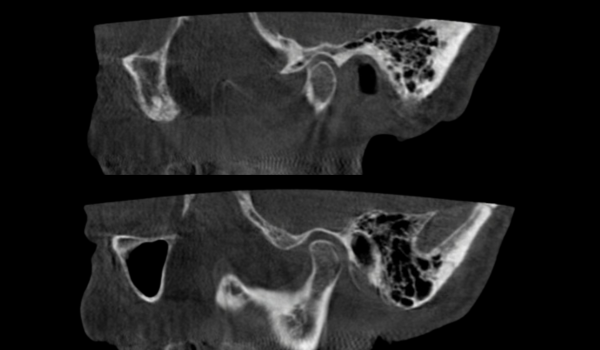

3д діагностика скронево-нижньощелепних суглобів

Блок 1. 3д діагностика скронево-нижньощелепних суглобів

✅ Нормальна анатомія СНЩС на КПКТ

✅ Розміри голівки СНЩС, рентгенологічна суглобова щілина

✅ Диференційна діагностика дегенеративних змін СНЩС. Клінічні приклади

✅ Дислокації голівок СНЩС. Клінічні приклади.